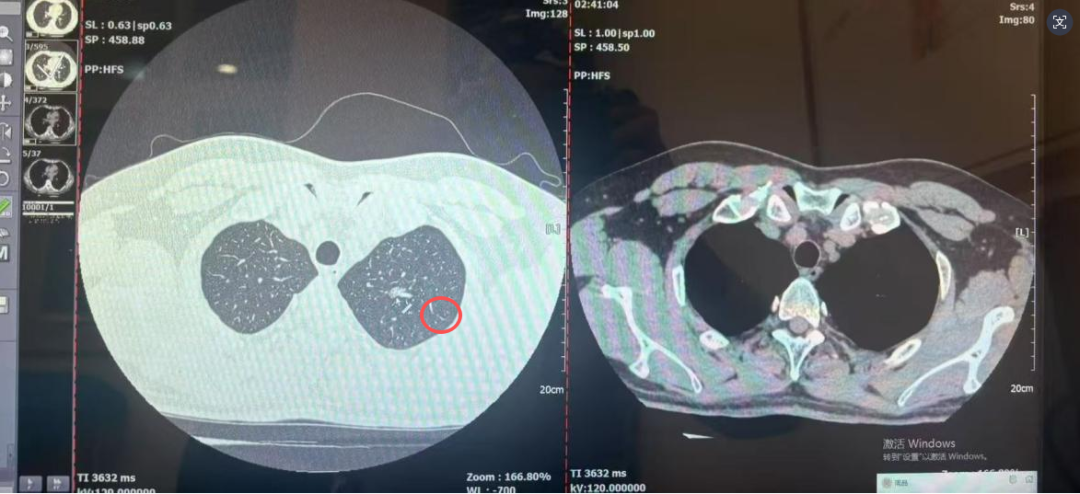

日前,刘先生不小心受凉感冒,咳嗽一直没好利索。想着排查下是不是合并了肺部感染,他便到西安医学院第一附属医院做了胸部 CT 检查。本以为只是常规检查,结果报告上的一句话让他瞬间慌了神:左肺上叶尖后段发现一个10mm×6mm的混合密度结节影。

“从你的症状看肺结节为感染性病变的可能不大,此次患病也与结节无关。考虑肿瘤病变可能。”呼吸与危重症医学科专家告诉刘先生;“你这结节是混合密度,形态上有恶性特征,大概率是早期肺癌,但不用怕,幸亏发现得早。”影像科专家指着CT影像说;心胸外科专家接着补充:“这个位置适合做胸腔镜微创手术,创伤小、恢复快”;病理科专家也耐心说明:“手术切除后我们会做病理检查,最终确认结节性质,为后续治疗提供准确依据”。